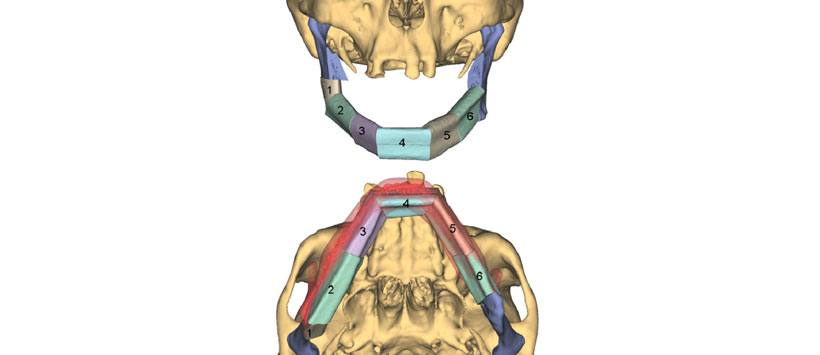

La resección mandibular virtual fue seguida por la reconstrucción virtual del defecto mandibular resultante con un colgajo de peroné que consta de seis segmentos. Este procedimiento semiautomático consistió en dividir el defecto del hueso mandibular en seis unidades con el fin de posicionar los segmentos de peroné de tal manera que pudieran llenar el defecto de manera apropiada. Después de determinar los extremos distales y proximales del sitio de osteotomía fibular, el colgajo de peroné se colocó virtualmente en el defecto utilizando un algoritmo de software (Fig. 3). Como un peroné es un hueso recto, se deben cortar cuñas del hueso para permitir que se cree la forma deseada de la mandíbula. Las líneas y los ángulos de osteotomía fueron determinados automáticamente por el software (Fig. 4). Después de un posicionamiento rugoso automático de las piezas de hueso, el ingeniero de planificación colocó manualmente los segmentos de peroné en su posición exacta al final del procedimiento de reconstrucción mandibular virtual.

Luego se utilizó un modelo virtual de la mandíbula reconstruida que se había generado sobre la base de la planificación asistida por computadora para la planificación asistida por computadora de una placa de reconstrucción utilizando el software CAD patentado por DePuy Synthes. La posición de la placa a lo largo de la superficie externa del modelo virtual de reconstrucción mandibular fue definida por el ingeniero (DePuy Snythes) de acuerdo a la planificación de los cirujanos. Luego, una placa de 2.5 mm se formó virtualmente sobre la base del modelo utilizando un algoritmo de software especial. Se pueden seleccionar diferentes números, tamaños y ángulos (máximo: 15 grados) de orificios para tornillos (Fig. 5). La placa descrita aquí tenía 24 agujeros. Los agujeros en las regiones de la rama derecha e izquierda estaban angulados (15 grados) en dirección craneocaudal (Fig. 5). Además, la longitud requerida o deseada de cada tornillo se determinó mediante simulación por computadora. En el caso presentado aquí, se colocaron tornillos bicorticales en el hueso mandibular residual y tornillos monocorticales en los segmentos de peroné.